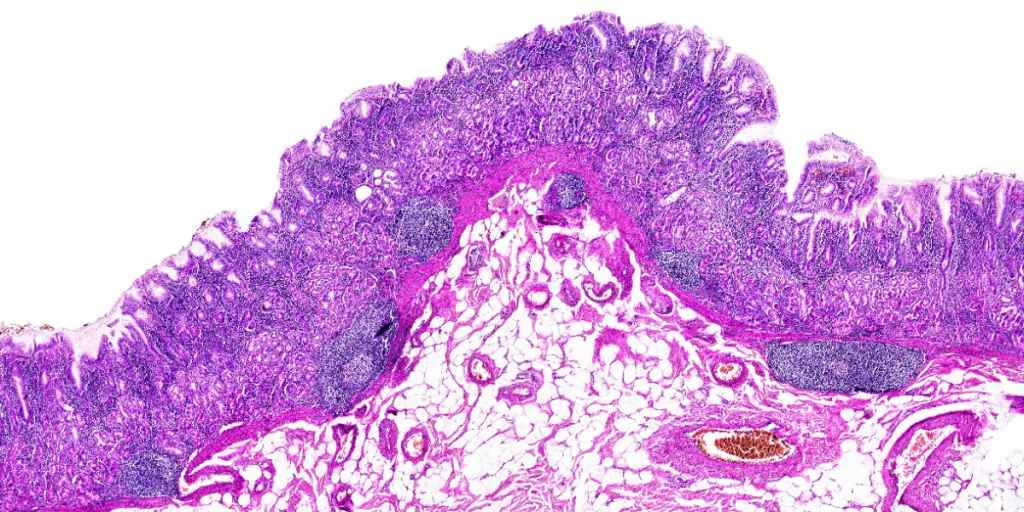

Staining Techniques

To overcome the lack of natural pigments, specimens are often prepared with a stain. There are many different stains which are used to distinguish different parts of a cell. Staining is commonly used in tissue samples.